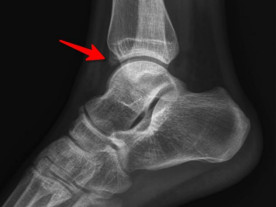

前方長(zhǎng)骨刺

幾經(jīng)輾轉(zhuǎn),李先生來到廣安醫(yī)院就診,骨科中心主任羅軍副主任中醫(yī)師為他進(jìn)行了詳細(xì)專業(yè)的查體,結(jié)合影像檢查,診斷為右踝關(guān)節(jié)不穩(wěn)(距腓前及跟腓韌帶斷裂)、右踝關(guān)節(jié)創(chuàng)傷性關(guān)節(jié)炎。羅軍主任帶領(lǐng)大家詳細(xì)分析病情之后,決定為他施行踝關(guān)節(jié)鏡下病變組織清理和距腓前韌帶、跟腓韌帶重建術(shù)。

踝關(guān)節(jié)鏡見前方長(zhǎng)骨刺

醫(yī)生們?cè)谑中g(shù)中發(fā)現(xiàn),李先生的右踝關(guān)節(jié)軟骨損傷明顯,踝關(guān)節(jié)前方及內(nèi)外側(cè)均有不同程度的骨質(zhì)增生,相互撞擊引起疼痛,同時(shí)距腓前及跟腓韌帶斷裂。手術(shù)醫(yī)生利用磨鉆,小心翼翼將引起撞擊的骨刺一一去除,然后,修復(fù)了損傷的關(guān)節(jié)軟骨,最后,為他完成了距腓前和跟腓韌帶的修復(fù)。